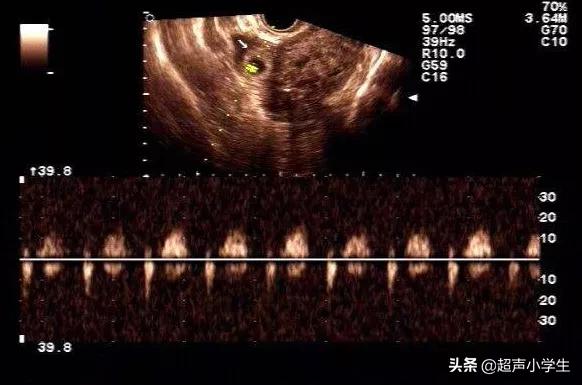

超音波検査では、芽の大きさ(7週で長さ9.3mm)を測定し、正常かどうかを確認することもできます。胎児の心臓を確認するのもこの時期で、すでに原始的な心拍があれば正常です。

次に、腹部超音波検査

胎児の心音は、7週ごろの超音波検査ではっきりと聞くことができ、はっきりとしたリズムのパターンがあります。どうしても心配な場合は、試してみてもいいかもしれません。

私も7週目に最初の超音波検査を受けに病院に行きましたが、その時点では子宮内妊娠初期というだけで、芽も心拍もありませんでした。

医師は10日後に再検査に行くように言った、私は10日目に再検査に行った、芽と心臓があり、私の心臓は即座にリラックスしていた、あなたはあなたの赤ちゃんが安全かどうかを確認したい、あなたは超音波検査のために病院に行くことをお勧めします、チェックはあなたの尿を保持する必要があります.あるいは、血液検査でHCGの値を確認し、安全であれば、8週目に胎児の芽と胎児の心臓をチェックする。

胎芽と胎児の心拍数を調べ、2カ月余りで超音波検査を受けると、胎児の心臓が鼓動する音を聞くことができる!